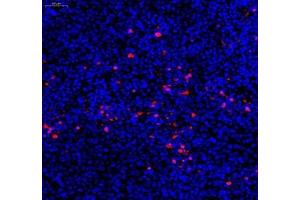

Caspase 3 抗体

(Caspase 3 (CASP3))

This gene encodes a protein which is a member of the cysteine-aspartic acid protease (caspase) family. Sequential activation of caspases plays a central role in the execution-phase of cell apoptosis. Caspases exist as inactive proenzymes which undergo proteolytic processing at conserved aspartic residues to produce two subunits, large and small, that dimerize to form the active enzyme. This protein cleaves and activates caspases 6, 7 and 9, and the protein itself is processed by caspases 8, 9 and 10. It is the predominant caspase involved in the cleavage of amyloid-beta 4A precursor protein, which is associated with neuronal death in Alzheimer's disease. Alternative splicing of this gene results in two transcript variants that encode the same protein. [provided by RefSeq, Jul 2008].